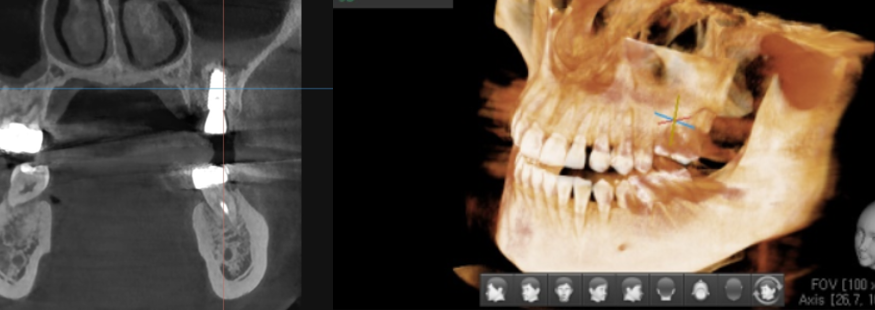

디지털 임플란트 시에는 ct 장비를 통해 분석을 하고

수술에 들어갑니다.

- 분석 > 수술

또한 임플란트가 들어갈 위치

식립 각도를 예측하여 개인 맞춤형 수술을 진행하였습니다.

위에 환자분은 잇몸 뼈가 부족하여

상악동을 들어 올리고 뼈이식을 하셔야 하는 환자분이었는데요

개인별로 다른 구강환경을 분석하여 미리 예측

잇몸도 최소로 절개할 수 있고

미리 분석한 자료를 토대로 30분 이내의 빠른 수술이 가능했습니다.